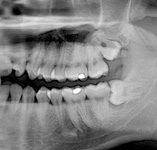

Zuby moudrosti (lidově „osmičky“) se zakládají v čelistech jako poslední zuby kolem 8. roku života a zpravidla prořezávají do dutiny ústní po 17. roce života. Proto velice často není místo pro jejich zařazení do správné polohy a zůstávají částečně nebo úplně skryté v kosti. Mohou být různě skloněné či zdeformované. Dále mohou nepříznivě působit i na sousední zuby či okolní měkké tkáně kolem čelistí a vyvolávat bolestivé záněty.

Jejich odstranění je někdy jednoduché, někdy obtížnější. Vždy je potřeba provést jejich odstranění v období, kdy jsou v klidu bez známek akutního zánětu (otok, bolest, teplota…).

Vyšetření pomocí tohoto přístroje používáme i ve stomatochirurgii (zlomeniny čelistí, zuby moudrosti, cysty, onemocnění čelistního kloubu), ortodoncii (retinované zuby, nadpočetné zuby), parodontologii atd.